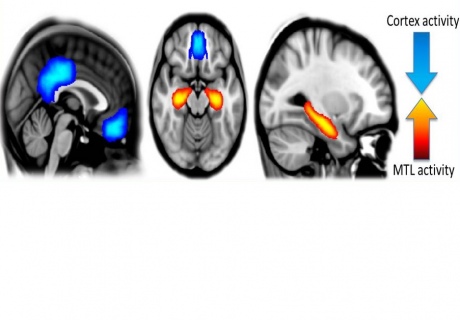

Reveló que, bajo los efectos de la psilocibina, aumentaba la actividad en la red más primitiva del cerebro, que está vinculada al pensamiento emocional.

Esta activación pronunciada implicó a varias regiones de dicha red al mismo tiempo, como el hipocampo (asociado a la memoria y la emoción) o la corteza cingulada anterior (relacionada con los estados de excitación).

Por otra parte, en los voluntarios sometidos al estudio se detectó una actividad más inconexa y descoordinada en la red cerebral vinculada al pensamiento avanzado, que hace posible, por ejemplo, que tengamos autoconciencia.

Reveló que, bajo los efectos de la psilocibina, aumentaba la actividad en la red más primitiva del cerebro, que está vinculada al pensamiento emocional.

Esta activación pronunciada implicó a varias regiones de dicha red al mismo tiempo, como el hipocampo (asociado a la memoria y la emoción) o la corteza cingulada anterior (relacionada con los estados de excitación).

Por otra parte, en los voluntarios sometidos al estudio se detectó una actividad más inconexa y descoordinada en la red cerebral vinculada al pensamiento avanzado, que hace posible, por ejemplo, que tengamos autoconciencia.

Actividad cerebral bajo el efecto de la psilocibina, con una reducción (en azul) de la actividad en las regiones cerebrales evolutivamente avanzadas, y una reducción (en naranja) en los centros de memoria y emoción. Fuente: Imperial College de Londres.